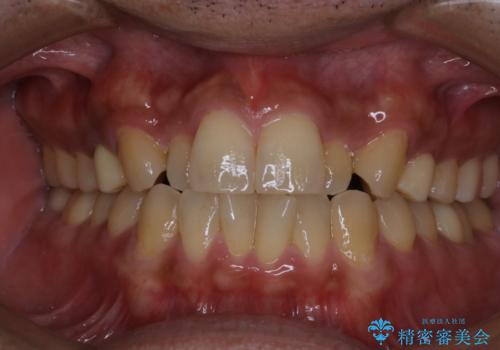

矯正治療を終えてのクリーニング